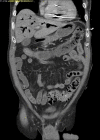

Venous air embolism (VAE) occurs when air is introduced into the venous system and subsequently travels into the right heart and pulmonary circulation. VAE mainly occurs from air that is forced by positive pressure or drawn in by negative pressure. We present a rare case of fatal VAE that occurred during a routine dental root canal procedure. A 69-year-old male was undergoing a root canal procedure at an outpatient dental office under local anesthesia. During the procedure, he went into cardiopulmonary arrest. He was resuscitated, and return of spontaneous circulation was achieved. Thoracic computed tomography was performed and revealed large amounts of air within the right ventricle and portal venous system. VAE should be recognized as a potentially fatal complication resulting from routine dental procedures.